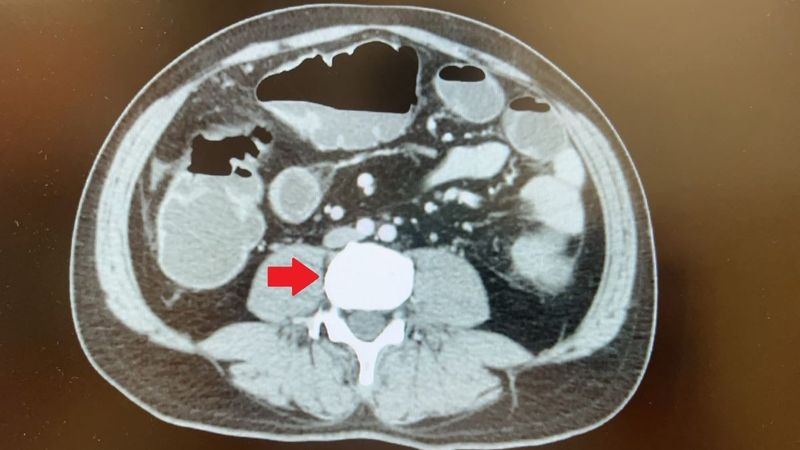

據國健署資料統計,大腸癌連續多年位居國人癌症發生人數之首,電腦斷層檢查看到降結腸處有一顆5公分的大腫瘤造成腸阻塞。(圖/台北慈濟醫院提供。)

向來健康,沒有家族史的45歲蘇先生,日前長達三天都無排氣、排便,因而腹脹無法進食,至台北慈濟醫院急診就醫。電腦斷層檢查發現他降結腸處有一顆5公分的大腫瘤,導致腸道完全阻塞。醫療團隊高度懷疑大腸癌,但由於腸阻塞無法施行大腸鏡檢查,在與病人討論後,大腸直腸外科陳昱廷醫師為他安排手術切除腫瘤、周圍腸段及淋巴節,術後病理報告確定為已有淋巴轉移的大腸癌第三期,進一步安排後續化學治療。